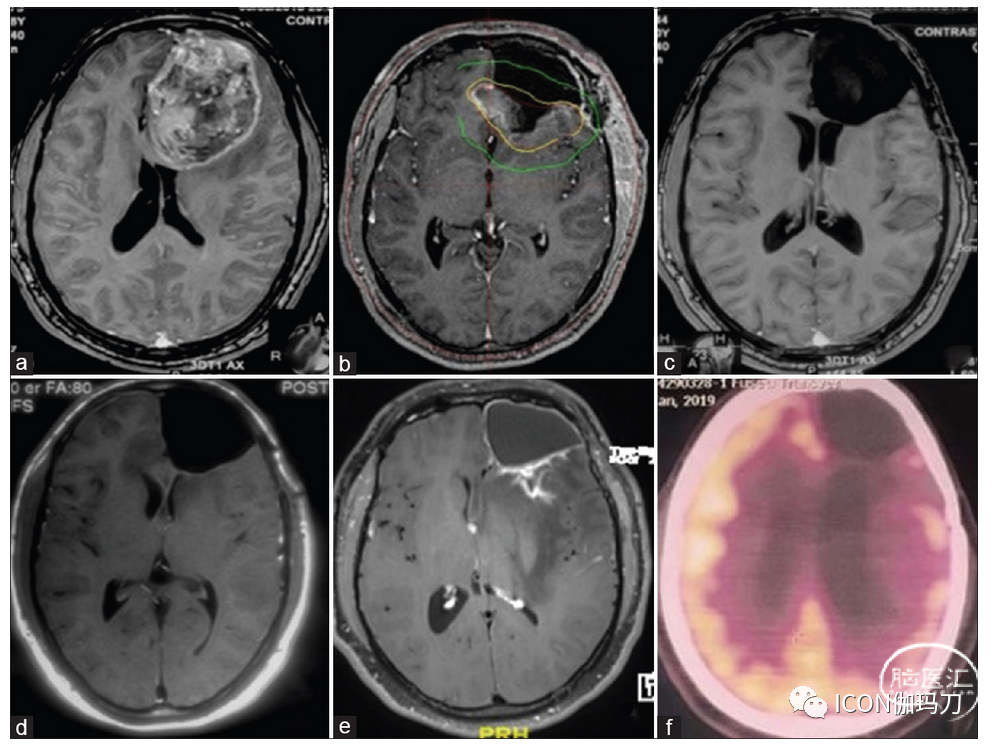

[图4]显示了一名GKT/TMZ组患者,随访2年PET扫描未显示FDG摄取,未发现肿瘤残留。

图4:(表2中的患者5)(a)术前CEMRI脑轴向切片显示左侧额部大块GBM。(b)GKT前CEMRI显示左侧额叶切除腔和残留肿瘤。(c和d) 6个月和1年的CEMRI分别显示肿瘤完全消退。(e) 2年的CEMRI显示PET-CT证实的放射性坏死(f),未显示FDG摄取。